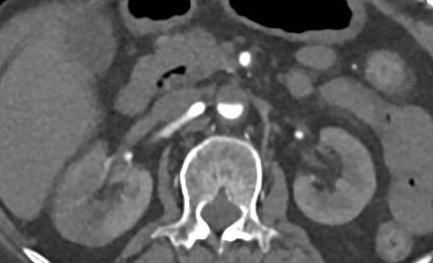

通过强化CT检查发现,患者腹主动脉肾动脉以远、左肾动脉及肠系膜下动脉开口处、双髂动脉及双侧下肢动脉血栓形成,右肾斑片状弱/无强化影,提示右肾梗死(图3-5)。

图3

图4

图5